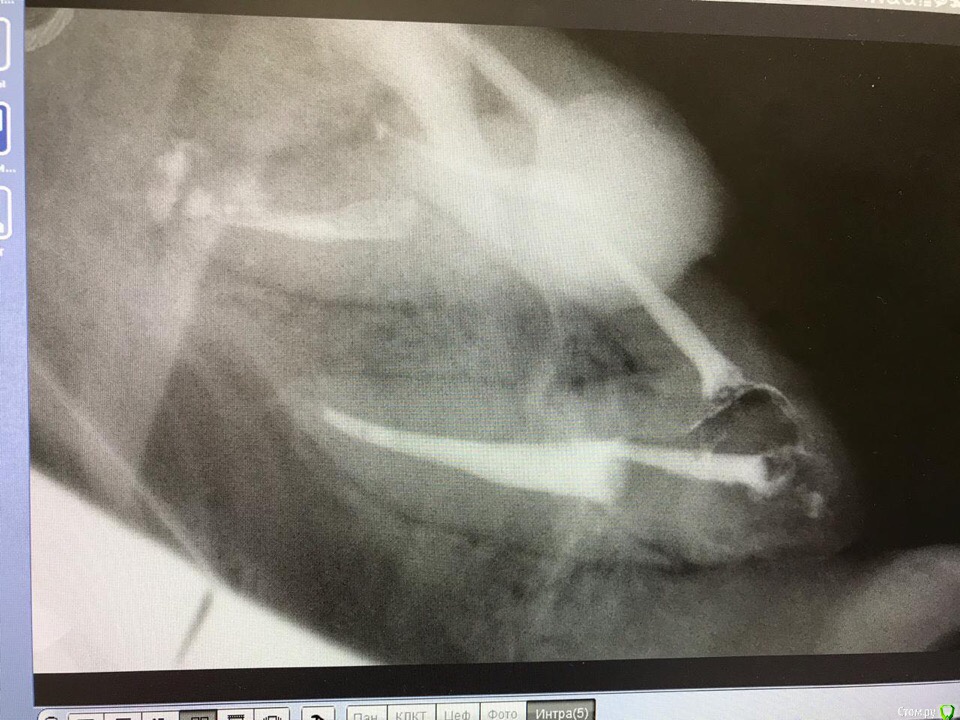

1586Doc Опубликовано 3 мая, 2019 Поделиться Опубликовано 3 мая, 2019 Еще раз спасибо за ответ.Подскажите .Сразу купить не могу и инжектор и плагер. Стоит выбор что первое.Пломбировка чисто инжектором думаю у меня не приживется. Может купить термоплагер и чисто вертикалить? на сколько это ускорит работу в сравнении с латералкой?тут скорее вопрос насколько вы качественно делаете латеральную. Если делать ее как положено времени уходит много. Я использую комбинированный метод. Когда приноровился, выходит достаточно быстро. Расход очень не большой, качество пломбировки значительно выше (часто вижу ответвления теперь на снимкахЕще Вам понадобится большое количество Машту разных размеров 2 Ссылка на комментарий

St. Опубликовано 9 мая, 2019 Поделиться Опубликовано 9 мая, 2019 (изменено) Еще раз спасибо за ответ.Подскажите .Сразу купить не могу и инжектор и плагер. Стоит выбор что первое.Пломбировка чисто инжектором думаю у меня не приживется. Может купить термоплагер и чисто вертикалить? на сколько это ускорит работу в сравнении с латералкой? рада помочь!Покупайте только термрплагер, он 100% нужен и улучшает качество, без инжектора во многих случаях можно обойтись. По методике латералка + термоплагер очень хорошо получается, времени не сэкономите но качество будет . (комбинированная методика Соломонова, почитайте)Вертикалка лично у меня не особо прижилась. Что касается холодных плагеров, то у меня типа как на 1 картинке (набор из 4 шт), одна сторона меньшего диаметра тонкий гибкий ни-ти, вторая толстый стальной. Размеры 35-70, 40-80, 50-100, 60-120. Последний использую крайне редко.Есть наборы с меньшим ассортиментом, но ими не работала. Изменено 9 мая, 2019 пользователем St. Ссылка на комментарий